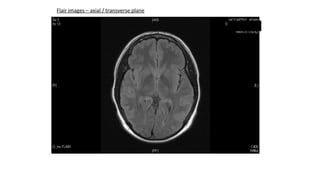

Flair images – axial / transverse plane

Flair images –axial / transverse plane